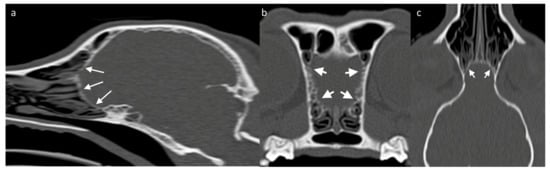

Assessing the surrounding bony structures—namely, the lamina cribrosa—can be the best approach to the OB through CT [73], which shows a thin mineral-attenuating curved plate with small perforations visible on high resolution reconstructions (Figure 4). Determining the detailed volume and shape of a structure as small as the OB itself should favor the use of high-resolution MRI. Since the OB is positioned within the olfactory fossa of the ethmoid bone, there is a risk of susceptibility artifacts which lead to regions of artifactual signal void. Susceptibility artifact arises here from distortions in the magnetic field homogeneity, particularly due to the proximity of paramagnetic air in the adjacent frontal sinuses. Patients with smaller frontal sinuses (such as brachycephalic breeds) are affected to a lesser extent than small patients with relatively large frontal sinuses, such as cats [74]. In clinical practice, the use of T2-weighted sequences is common as the contrast between the OB tissue and the surrounding CSF allows the structure to be better defined [51].

Figure 4. CT skull of a 3-year-old Jack Russell Terrier, acquired as a volume and reconstructed in a high frequency reconstruction algorithm, displayed in a bone window. (a) Sagittal/slightly parasagittal reconstruction to line through with the OB; (b) Transverse plane at the level of the OB; and (c) Dorsal plane reconstruction at the level of the OBs. White arrows on each image highlight the thin curved lamina cribrosa (cribriform plate) that bounds the rostral aspect of the OBs. Multiple tiny defects through which the olfactory nerve bundles pass are visible in all planes, although most distinct on the transverse plane compared to the remaining ones.